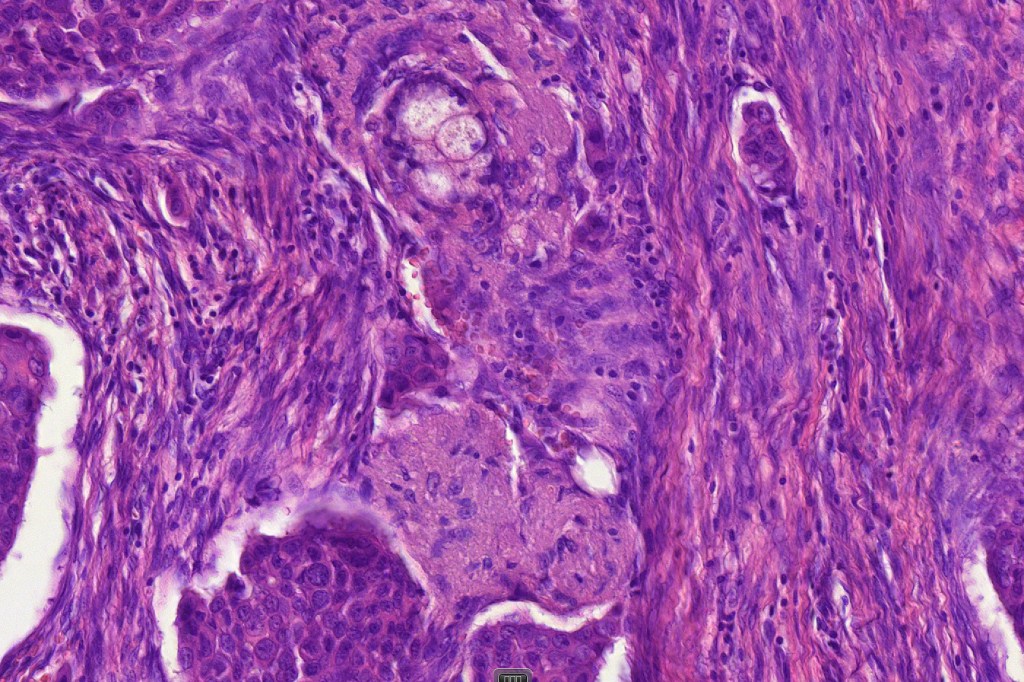

Histological features

•Poorly circumscribed tumor nodule with invasive border

•Variable glandular, tubular, papillary, tubulo-papillary, diffuse and solid growth patterns

•Large cells with vesicular nuclei and often prominent nucleoli

•Decapitation secretion

•Variable pleomorphism, mitotic activity & atypical mitoses

•Variable necrosis

•Variable lymphovascular involvement & perineural infiltration